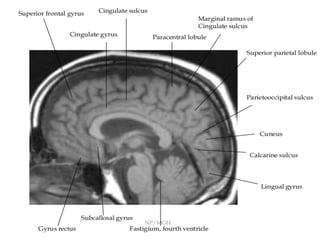

-Sagi<al	T1	image-	Parallel	to	the	corpus	callosum,	the	cingulate	sulcus

(arrowheads)	as	it	approaches	the	splenium	turns	towards	the	brain	surface.

This	extension,	the	pars	marginalis	of	the	cingulate	sulcus,	lies	immediately

posterior	to	the	central	sulcus.

Bracket	sign-	Bihemispheric	symmetrical	part	of	pars	marginalis	od	cingulate

sulcus	shows	anteriorly	open	bracket.

cingulate	sulcus

Central	sulcus

Sylvian	fissure